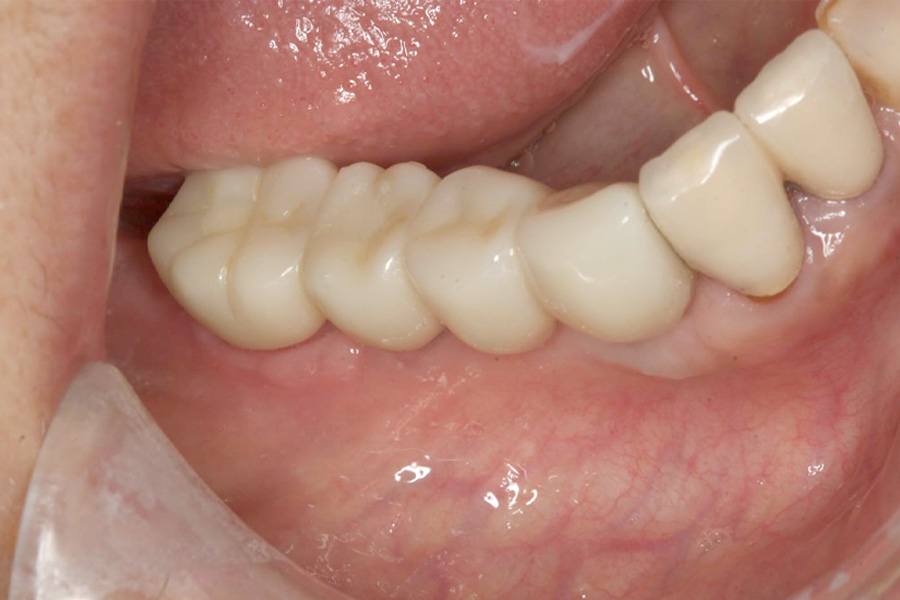

治療後

治療後症例写真

ブリッジの土台にしていた歯の保存ができなくなり、再治療を行いました。

右下3番、7番の抜歯後、右下3番、5番、6番相当部分にインプラントを3本埋入し、補綴を行いました。